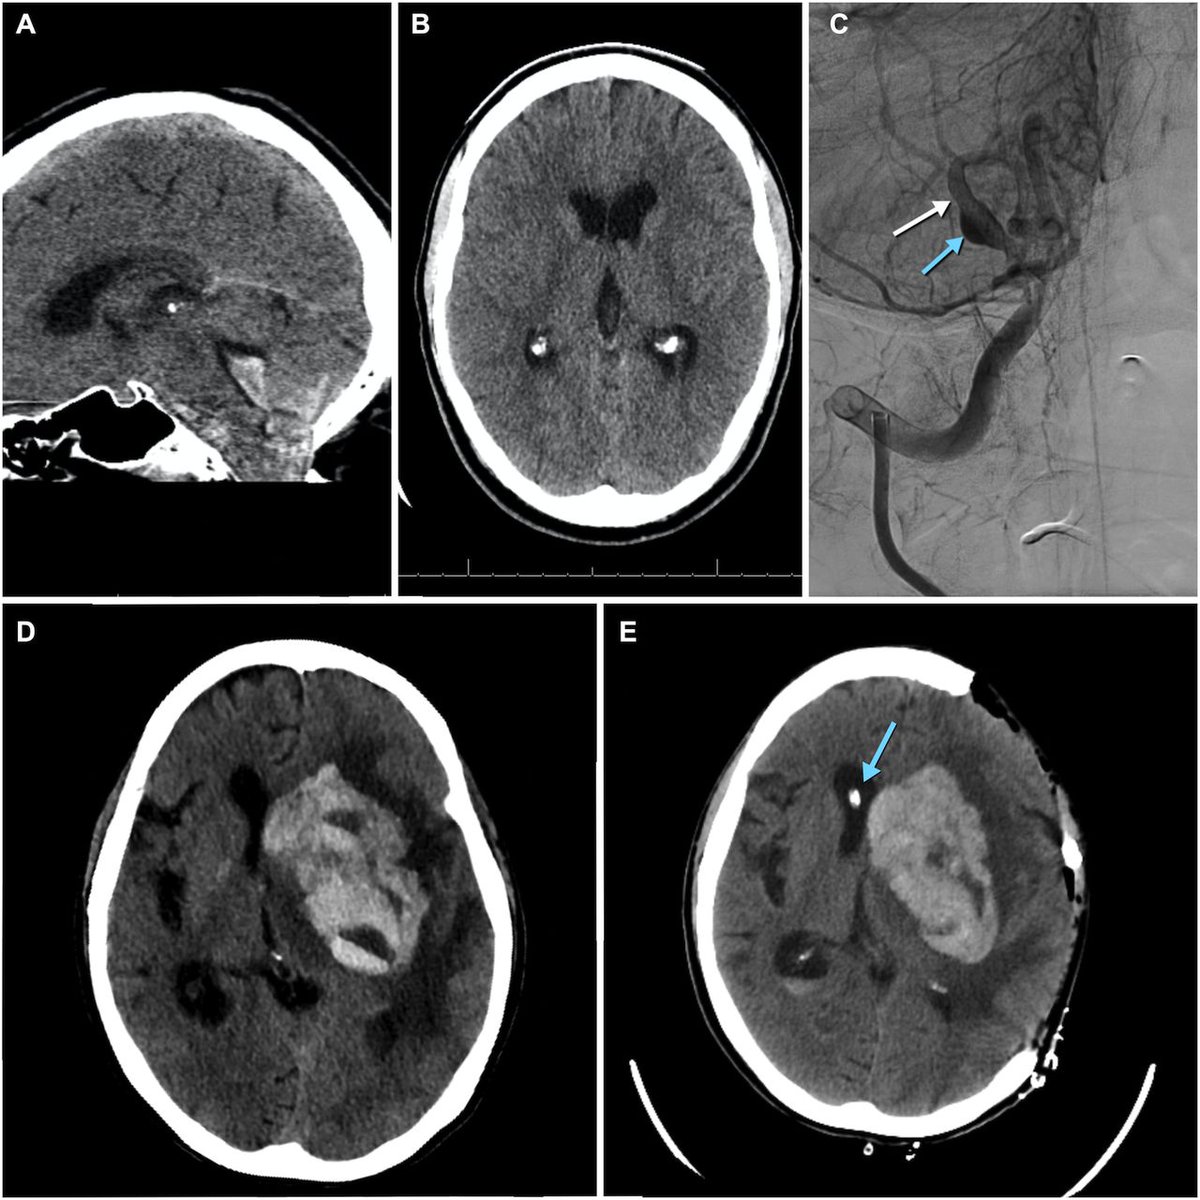

COVID-19 and the brain: a new study. What the study looked at - Researchers examined autopsies of 13 people who died with COVID-19 vs 23 controls. Goal: to uncover what exactly happens inside the brain during COVID-19.🧵